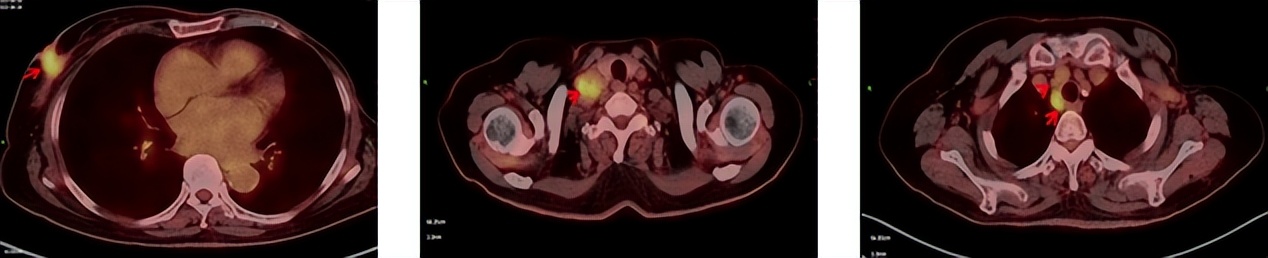

2023.6.26复查PET-CT

1.右乳外上象限乳腺癌病灶(22*16mm),对比2023-04-14 CT(26*24mm)较前缩小,FDG代谢活跃。右侧腋窝小淋巴结(5mm),较前稍缩小,代谢不活跃。右侧锁骨上区、上纵隔淋巴结转移瘤(24*18mm),现大小同前相仿,代谢活跃(SUV:6.7)。

2.现胃贲门部术后改变,术区未见明显异常活性灶。

3.左乳、左侧胶窝术后改变,未见明显异常活性灶。双肺小结节。考虑炎性结节可能,建议复查;双肺门及纵隔另反应性淋巴结。

患者已接受胃癌根治术,术后通过PET-CT对病灶情况进行了评估。目前患者采用哌柏西利联合氟维司群方案治疗,乳腺病灶已明显缩小,但锁骨上淋巴结、纵隔及肺门淋巴结未见缩小。为进一步为患者制定更精准的治疗方案,龚畅教授与曾银朵教授组织了第二次多学科联合会诊。